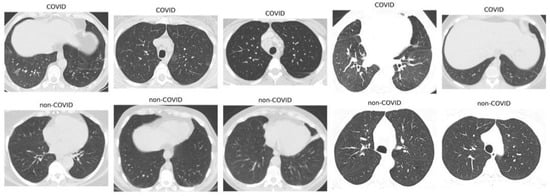

The SARS-CoV-2 CT Scan dataset, Figure 1, is publicly available on Kaggle. It consists of 1252 CT scans from patients diagnosed with SARS-CoV-2 infection (COVID-19) and 1230 scans from non-infected individuals, resulting in 2482 CT scans. Data were collected from actual patients in hospitals in São Paulo, Brazil [22]. In the context of COVID-19 image analysis, pre-processing techniques are important to enhance image quality, improve feature extraction, and increase the accuracy of machine learning and deep learning models.

Figure 1. Sample images of SARS-CoV-2 in CT scans.